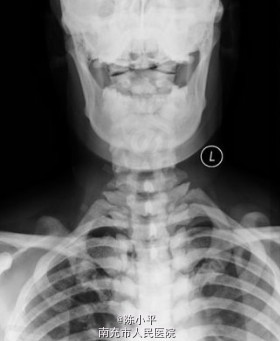

氟骨症一例

氟骨症

患者女,37岁,颈部不适检查时发现,加拍骨盆片,可见纱布眼状骨纹理,未见“同心环”影及腰椎“夹心蛋糕”征,结合职业史,诊断为氟骨症。